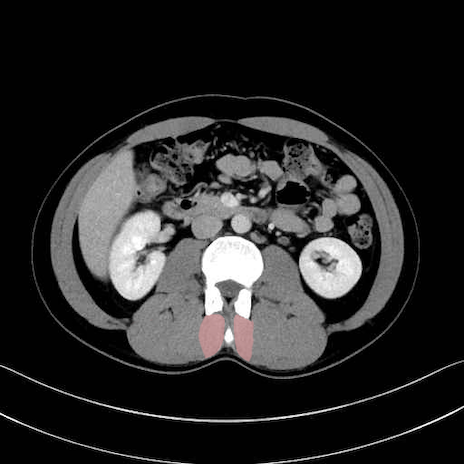

多裂筋 (Multifidus)